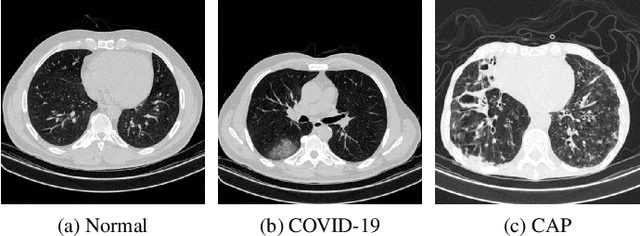

We propose a two-stage Convolutional Neural Network (CNN) based classification framework for detecting COVID-19 and Community-Acquired Pneumonia (CAP) using the chest Computed Tomography (CT) scan images. In the first stage, an infection - COVID-19 or CAP, is detected using a pre-trained DenseNet architecture. Then, in the second stage, a fine-grained three-way classification is done using EfficientNet architecture. The proposed COVID+CAP-CNN framework achieved a slice-level classification accuracy of over 94% at identifying COVID-19 and CAP. Further, the proposed framework has the potential to be an initial screening tool for differential diagnosis of COVID-19 and CAP, achieving a validation accuracy of over 89.3% at the finer three-way COVID-19, CAP, and healthy classification. Within the IEEE ICASSP 2021 Signal Processing Grand Challenge (SPGC) on COVID-19 Diagnosis, our proposed two-stage classification framework achieved an overall accuracy of 90% and sensitivity of .857, .9, and .942 at distinguishing COVID-19, CAP, and normal individuals respectively, to rank first in the evaluation. Code and model weights are available at https://github.com/shubhamchaudhary2015/ct_covid19_cap_cnn